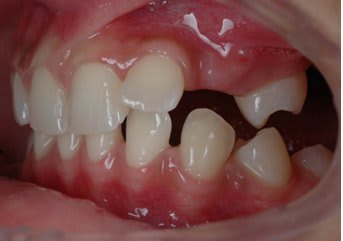

Et après environs un ans de traitement

Bingo

Il y avait ankylose de la 22 mais pas des molaires.

Sa se devine ici car le fil est quasiment droit ce qui signifie que sa forme c'est exprimé presque complètement.

Le problème étant que si la forme du fil est correct sa position ne l'est pas.

La 22 étant ankylosé elle a fonctionné comme un point d’appui et a fait bouger tout le reste.

Dans ce cas c'est impressionnant car la dent ankylosé

- était mal positionné en début de traitement

- Qu'il n'y avait aucun dent dans le secteur postérieur pour limiter les effet.

Le fil rond pouvait tourner dans le slot de 22, vue qu'il n'y avait pas de dent en postérieure rien n’empêchait la rotation du fil et donc l’aggravation de la malocclusion.

La 21 qui était proche a était la plus affecté sa se voit bien sur les photo avec bracket, elle a subit une importante rotation dans le sens mesio distal et a était procliner. Son changement de position a eu un impacte sur 21 puis sur 11 ect ect , les effets devenant de plus en plus faible a mesure que l'on s'éloigne.

On a eu une important proclination de l'ensemble des incisive.

Mais encore une fois ce qu'il faut noter c'est le changement important au niveau de 21 avec un FIL PARFAITEMENT DROIT au niveau des incisives